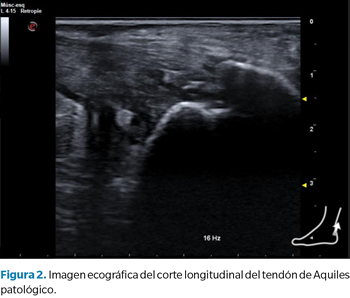

Esta aplicación de la ecografía como herramienta predictiva puede ser interesante desde el punto de vista de la investigación o incluso en la práctica clínica en determinados ámbitos como el deporte, con el objetivo de desarrollar planes de prevención si se encuentran alteraciones ecográficas significativas. Sin embargo, pensamos que en la práctica clínica “habitual” este uso de la ecografía no es tan aplicable ni útil como la ecografía que realizamos para la valoración morfofuncional o el uso como herramienta de feedback visual y guía de abordajes invasivos (Figura 2).